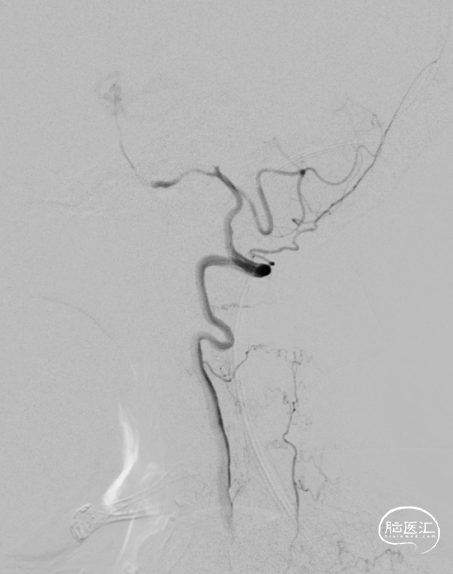

全脑血管造影DSA:双侧椎动脉起始段狭窄。远端供血不足。

8F导引导管到达锁骨下动脉。

微导丝通过椎动脉起始处狭窄段,到达椎动脉V3段。